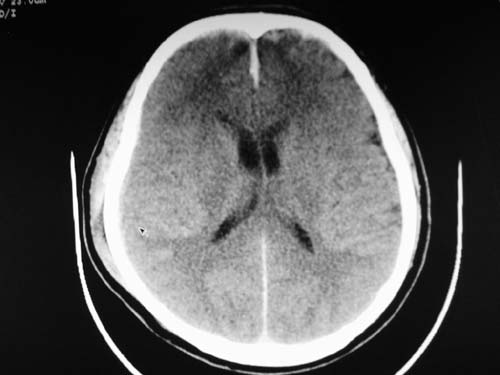

标题: CT17020:是硬膜下的吗?

脑中线内血肿,是硬膜下的吗?

脑中线内血肿——硬膜下血肿。

脑中线内血肿——硬膜下血肿。我们一般认为中线即可是硬膜下,也可是蛛网膜下腔的。边缘锐利,张力高的考虑硬膜下的,边缘模糊的,考虑下腔的。如果有老师有肯定的答案,麻烦下给我发个短信

这个病人年龄不小吧,右侧脑沟不清,中线结构稍有左移,右侧额颞顶及右镰旁硬膜下血肿,另有蛛血,骨折。

外伤后引起的颅骨骨折、硬膜下血肿、皮下血肿,颅骨骨折引起的矢状窦破裂,形成大脑纵裂内血肿。